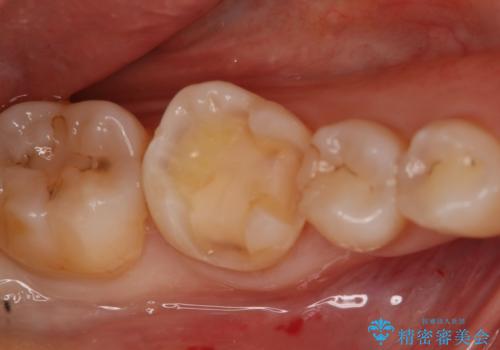

- 右下6番のメタルインレー脱離のため来院。

セラミックの治療を希望されたため切削量を考慮し、セラミックインレーでの治療を選択しました。

う蝕が深くまで進行していたので、CRで裏層した上で形成・印象をしています。